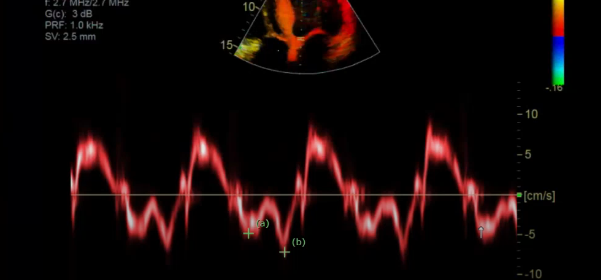

what is this measurement for

Septal side

measure the MV septal E

and then MV septal A velocity

gate should be 5-10